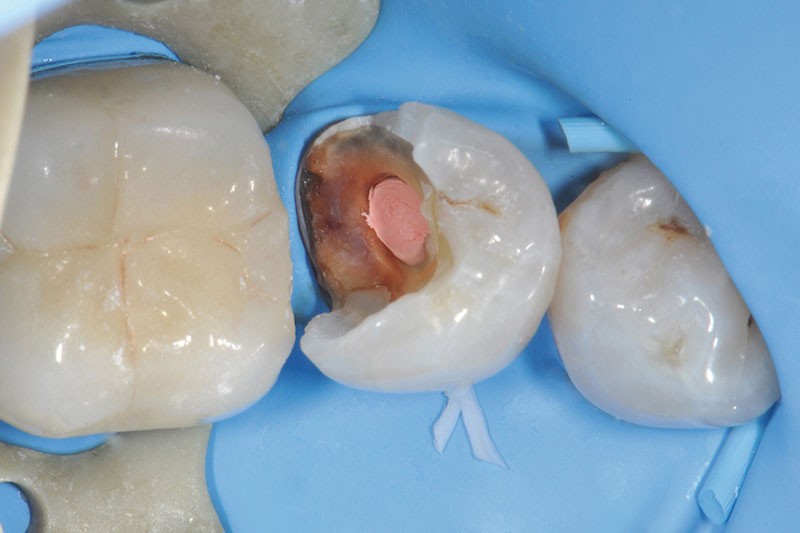

3, 4, 5. La restauration est déposée, les tissus carieux éliminés et la cavité d’accès aménagée avant la réalisation du traitement endodontique. La radiographie postopératoire permet de visualiser l’obturation du canal latéral en regard de la LIPOE.

6. Après réalisation de la préparation périphérique externe, la hauteur, la largeur et l’épaisseur des parois résiduelles sont évaluées, ce qui permet de poser l’indication d’une RMIPP (reconstitution par matériaux insérés en phase plastique).